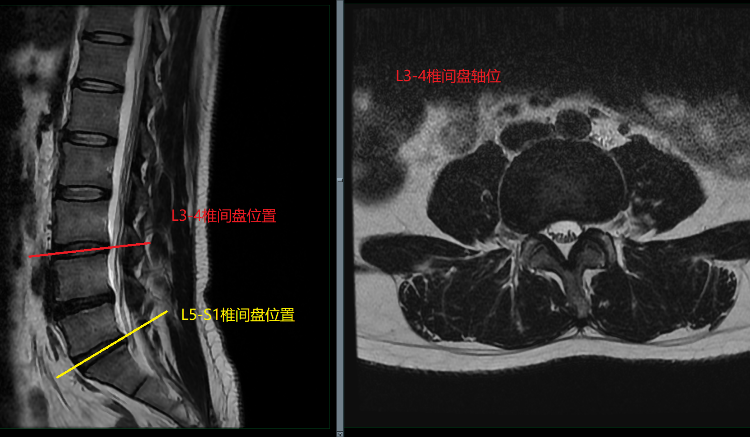

腰椎间盘轴位的解剖结构:腰椎间盘由三部分组成,中间是髓核,髓核之外包围着一圈纤维环,髓核上下各一软骨终板(也即正常椎间盘 = 上下软骨终板 + 纤维环 + 髓核)。

腰椎间盘 MR 评估需注意髓核、纤维环、后纵韧带等结构与神经根及硬膜囊的关系。